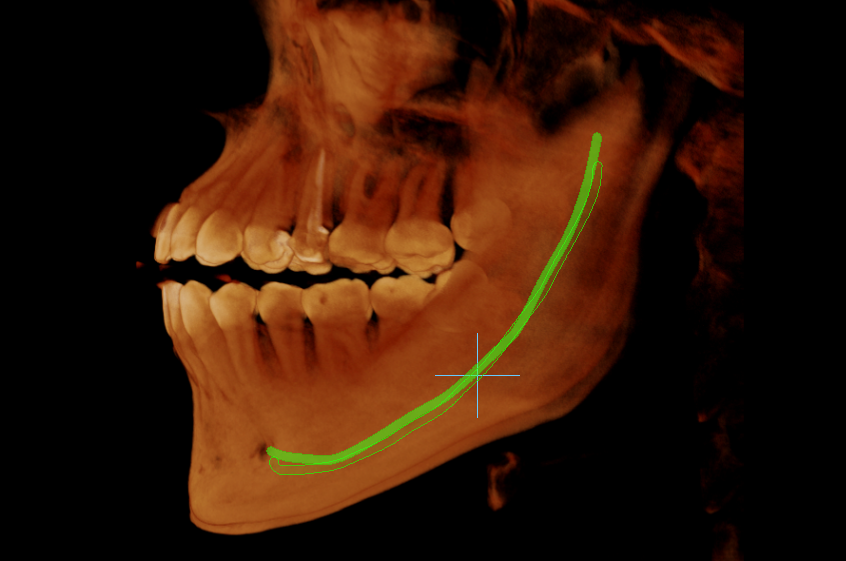

TOMOGRAFÍA DE TERCERAS MOLARES

Identifica la relación dentaria con el conducto mandibular y evitar complicaciones en el proceso quirúrgico.